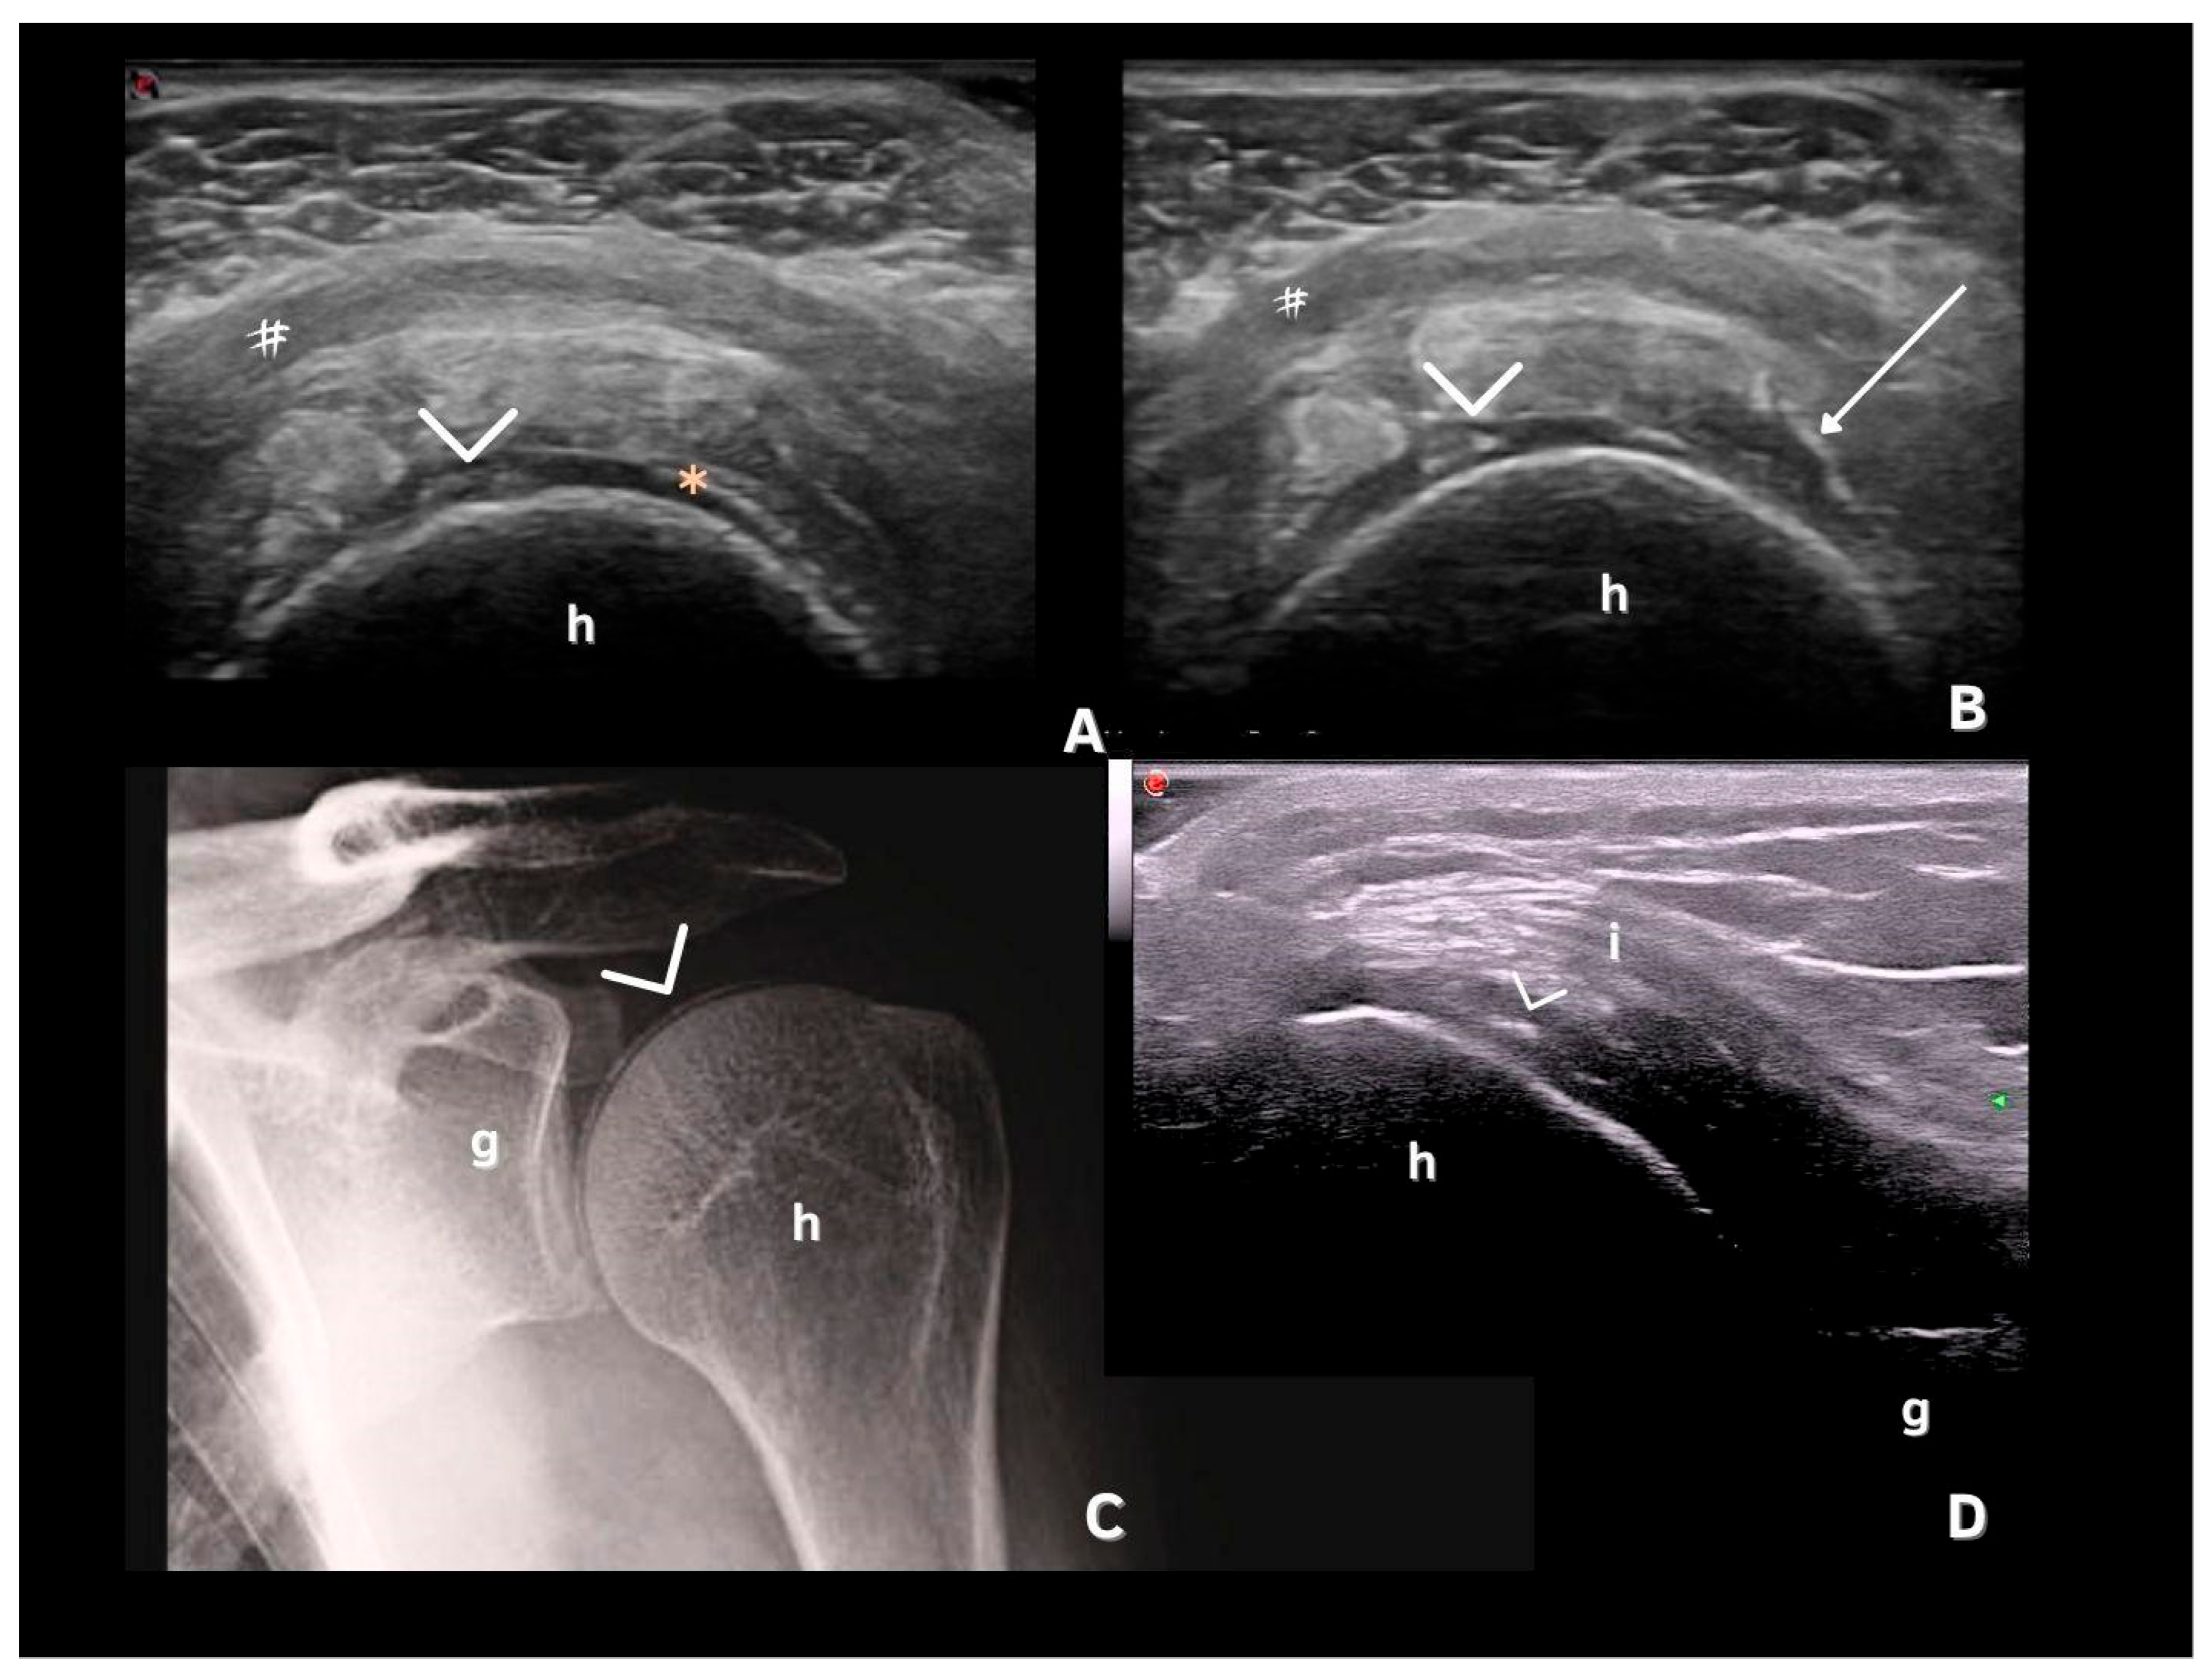

| Fibrocartilage | Shape: Deposits of variable shape. Echogenicity: Hyperechoic (similar to the bone cortex echogenicity). Localization: Within the fibrocartilage structure. Dynamic scanning: Remain fixed and move together with the fibrocartilage during dynamic assessment. Examples: Menisci, TFC, hip labrum, and acromioclavicular joint. |

| Hyaline cartilage | Shape: Deposits of variable shape. Echogenicity: Hyperechoic, without posterior shadowing. Localization: Localized within the hyaline cartilage. Dynamic scanning: The deposits remain fixed and move together with the hyaline cartilage. Examples: Knee and MCP joint. |